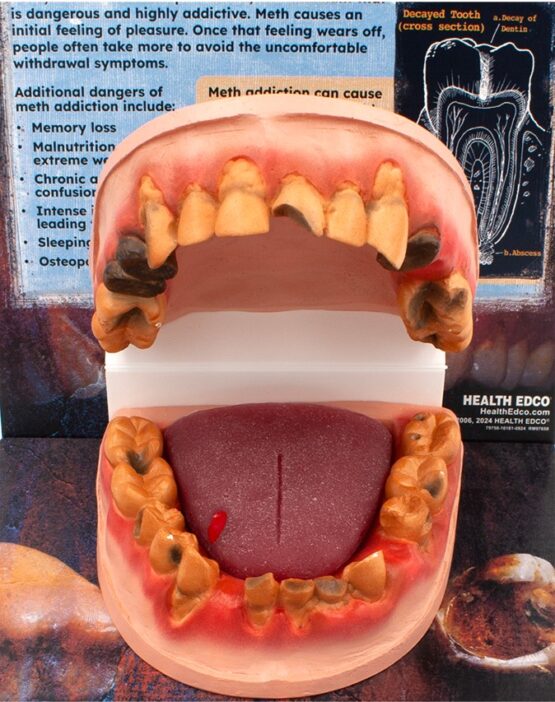

The 3-D, handpainted mouth model shows the oral consequences of meth use, such as missing teeth, severely decayed teeth, broken teeth, receding gums, and more. Also includes a tongue model with an ulcer.

Informative text explains how meth harms both the mouth and body and drives home the message that meth is a dangerous drug. 10″ x 10½” x 16½”.